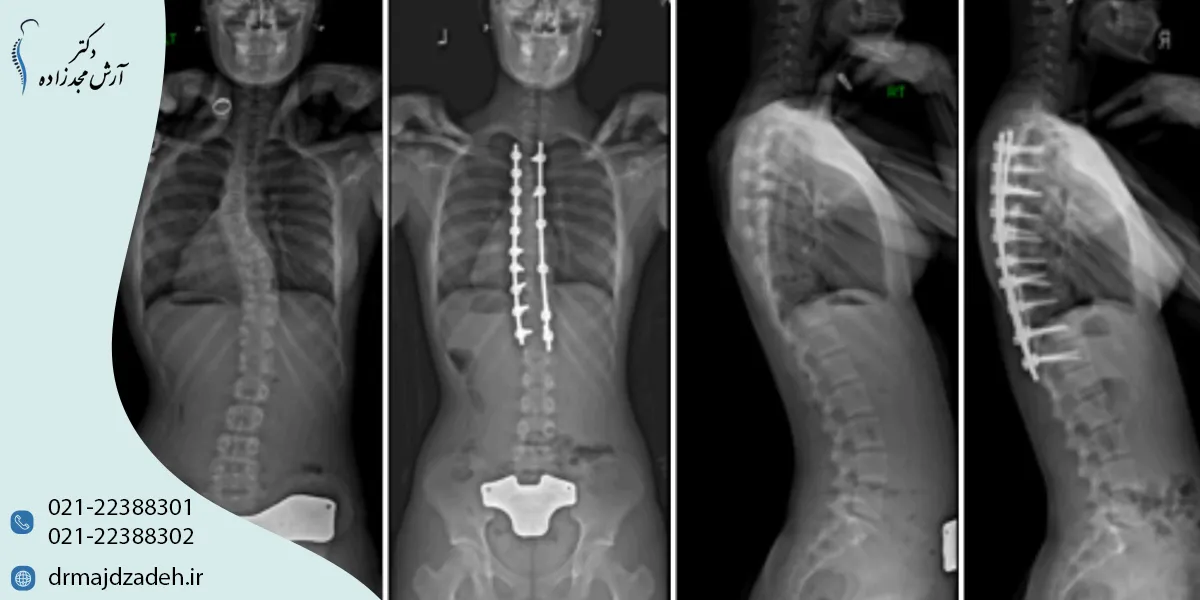

جراحی اسکولیوز؛ چه زمانی لازم است و چگونه انجام میشود؟

وقتی روشهای غیرجراحی مانند حرکات اصلاحی اسکولیوز یا اوزوندرمانی دیگر نتوانند جلوی پیشرفت انحراف را بگیرند، پزشک گزینهی جراحی اسکولیوز یا همان عمل اصلاح انحراف ستون فقرات را مطرح میکند.

در چنین شرایطی، هدف جراحی اسکولیوز تثبیت ستون فقرات، اصلاح زاویه انحراف، و جلوگیری از پیشرفت بیماری است.

مراحل عمل اسکولیوز و مدت زمان جراحی

عمل اسکولیوز یکی از جراحیهای تخصصی ستون فقرات است که بسته به نوع انحراف و تعداد مهرههای درگیر، میتواند بین ۴ تا ۸ ساعت طول بکشد.

این عمل تحت بیهوشی عمومی انجام میشود و معمولاً شامل چند مرحله کلیدی است:

- برش و دسترسی به مهرهها:

جراح از طریق پشت (Posterior Approach) یا گاهی از پهلو (Anterior Approach) به ستون فقرات دسترسی پیدا میکند. - اصلاح انحراف با ابزار مخصوص:

میلههای فلزی (Rods)، پیچها (Screws) و قلابها به مهرهها متصل میشوند تا ستون فقرات در وضعیت جدید و صحیح تثبیت شود. - فیوژن مهرهها (Spinal Fusion):

در این مرحله، استخوانهای پیوندی بین مهرهها قرار میگیرند تا بهتدریج با یکدیگر جوش بخورند و ستون فقرات یکپارچه شود. - بررسی نهایی اعصاب و پایداری:

در حین عمل، عملکرد عصبی با دستگاه مانیتورینگ بررسی میشود تا از عدم آسیب به نخاع اطمینان حاصل گردد. - بستن زخم و پانسمان:

پس از اطمینان از ثبات ستون فقرات، برش بسته و پانسمان انجام میشود.

طبق گزارش Hospital for Special Surgery (HSS)، بیماران پس از جراحی معمولاً ۳ تا ۵ روز در بیمارستان بستری میشوند و پس از آن میتوانند با مراقبت مناسب، فعالیتهای سبک روزانه را آغاز کنند.

مدت زمان و نتایج جراحی

مدت جراحی به میزان انحراف و تکنیک استفادهشده بستگی دارد. در اسکولیوزهای پیشرفته یا چندبخشی، عمل ممکن است طولانیتر باشد.

با رعایت اصول فیزیوتراپی پس از جراحی، حدود ۸۰ تا ۹۰ درصد بیماران بهبود قابلتوجهی در وضعیت بدنی و کاهش درد تجربه میکنند.